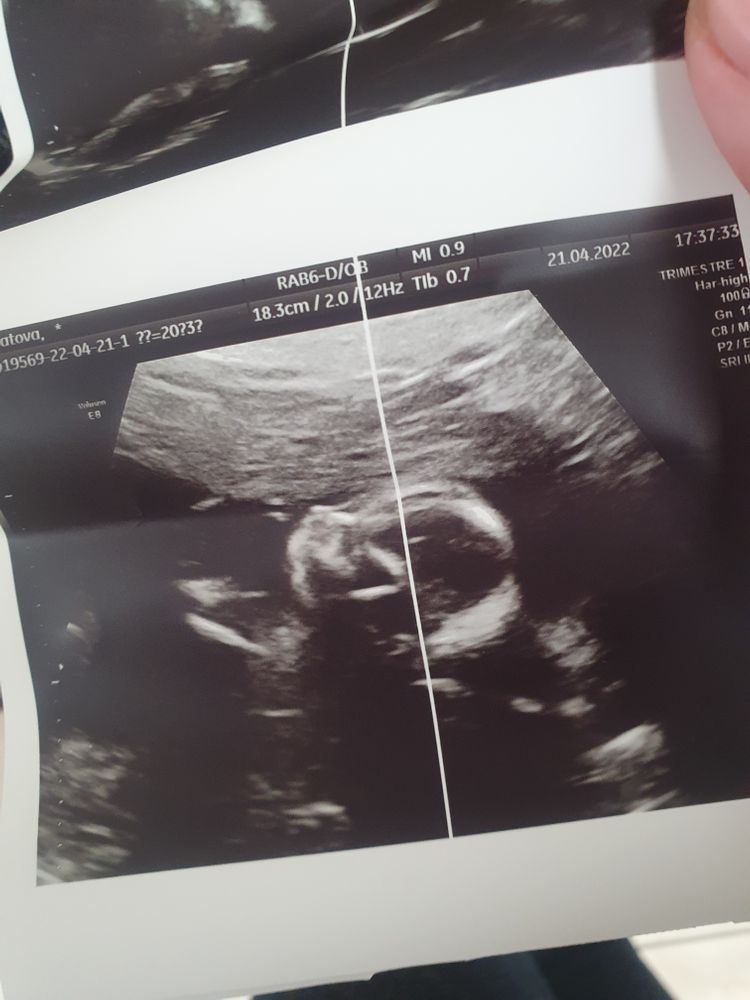

Прошли 2й скрининг, ждём мальчика🥰 Но есть пара вопросов...

В 20+4 прошла 2й скрининг, сказали,что мальчик 100%,уже ничего не отвалится🤣 Но есть некие странности. Перед этим была на узи в почти 17 недель,ходила,чтобы посмотреть пол. В заключение написано " Пуповина имеет 3 артерии". Кровоток не нарушен. Шов 5.6 мм(было экс 2 года назад). А сегодня на узи 2 артерии только и шов 1.8мм. И вот я теперь не понимаю,какому врачу верить?(была в двух разных клиниках платно). Если шов ещё может теоретически так истончится,но артерия в пуповине не могла же деться никуда? Оба узиста считаются лучшими в городе и аппараты тоже хорошие.